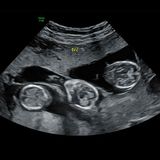

Marie přivedla na svět Charlieho, Lorinne a Laru, kterým je dnes osm měsíců, po léčbě metodou IVF. Lékaři jí přitom dávali jen pětiprocentní šanci, že se embrya uchytí. „Byl to fantastický výsledek,“ popsala nadšeně. „Nikdy jsem se nebála kvůli svému věku. Jsem velmi zdravá a v předchozích těhotenstvích jsem neměla žádné problémy,“ tvrdí.

S manželem už vychovávali čtyři syny, přesto se rozhodli zkusit ještě jedno dítě. Nečekali ale, že léčba vyjde hned napoprvé. „Nemysleli jsme si, že to vyjde na první pokus, proto jsme nechali přenést tři embrya, abychom zvýšili šanci,“ vysvětlila. „Řekli nám, že je jen pětiprocentní šance, že se uchytí, ale uchytila se všechna. Byla jsem v šoku a zároveň nesmírně šťastná. Byl to fantastický dar,“ říká pro What´s The Jam.

„Když jsem byla těhotná, břicho bylo jako velký kámen. Nemohla jsem cítit pohyby miminek, protože bylo uvnitř všechno strašně natěsno,“ popsala. Okolí navíc dlouho netušilo, kolik dětí čeká. „Lidé kolem jen viděli, že jsem těhotná. Nikomu jsme neřekli, že jsou tři, protože jsme nevěděli, jestli všechny přežijí. Pro všechny to byl šok.“